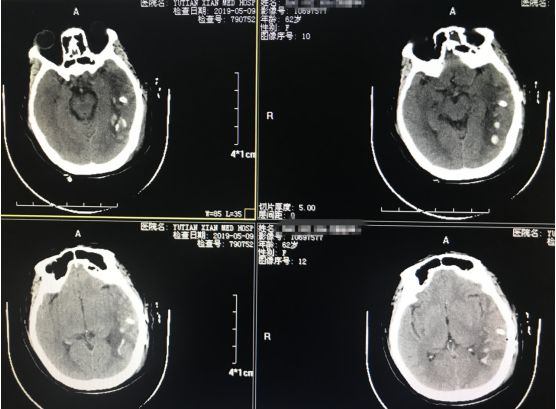

入院后行 “小骨窗开颅血肿清除术”,术后第2天患者神志清醒,问话能答,右侧肢体活动灵活。

▉术后第二天复查颅脑CT如图所示